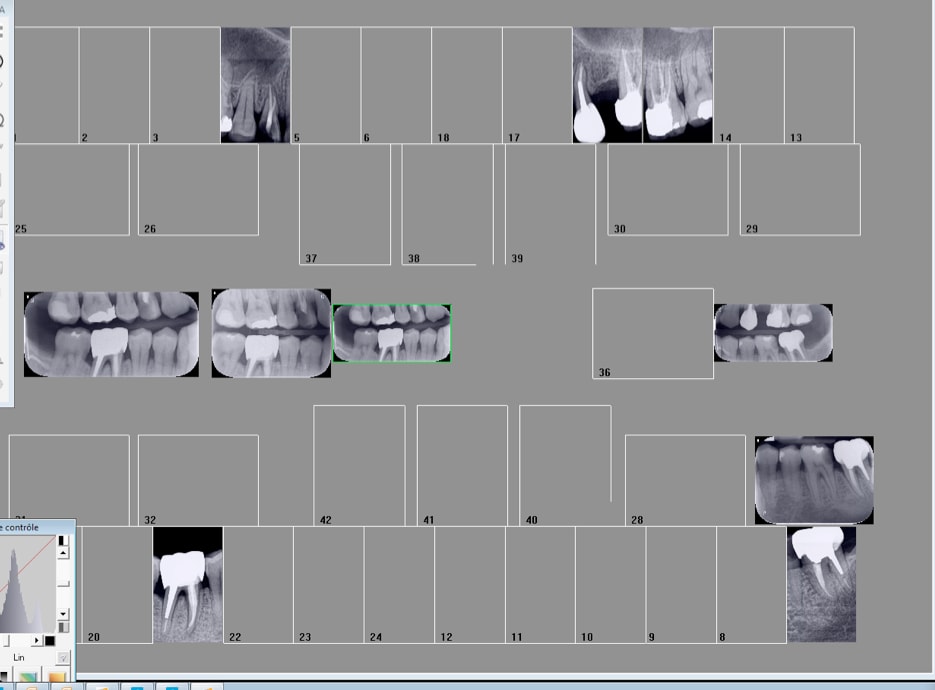

Ici on a du 2 du 3 en film agrémentés de quelques clichés de capteur RVG taille 1. -)

On va mélanger le nombre de radios, les formats et le nombre de secteurs pour noyer le poisson. Il y a une multitude d'emplacement libres sur mon FMS tuné. -)

Ca va ca va. de temps en temps on peine a à avoir les rebords alvéolaires because moins larges qu'un taille 2, mais dans l'ensemble c'est satisfaisant.

Tu as 4 secteurs dessus mais selon certains tu peux n'en compter qu'un alors que si tu utilises 2 taille 2 tu peux en compter 2 . Je suppose donc que si tu utilises 4 tailles 1 en vertical tu peux en compter 4. En suivant la logique hein ! -)

C'est moins net avec les tailles 3 je trouve notamment au niveau de l'os alvéolaire que tu es sensé avoir correctement. En taille 2 c'est plus propre. Ca double la dose de RX pour rien mais c'est plus propre. -)

Ca devient compliqué de coter sans tenir compte de la notion de secteurs quand on multiplie le format des films et qu'on mélange rétro coronaires et rétro alvéolaires, hein ? -)